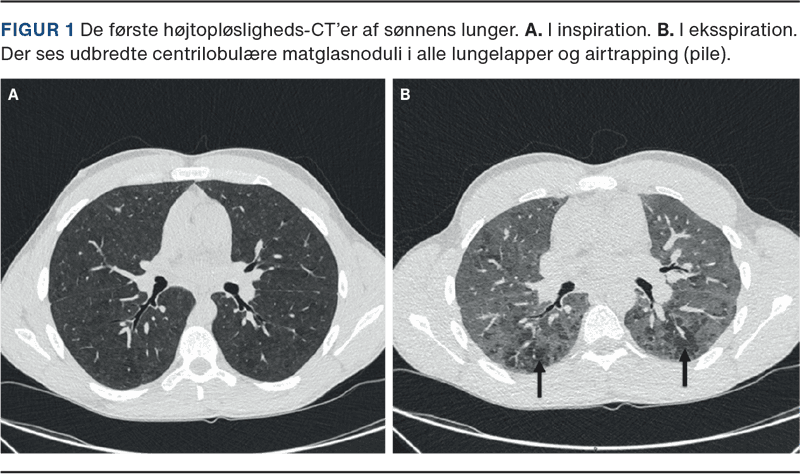

En 18-årig mand debuterede med funktionsdyspnø og tør hoste i 2021. Han var diagnosticeret med Aspergers syndrom og ikkeryger. I marts 2021 blev han indlagt med mistanke om akut forværring af astma. Han blev diagnosticeret med nonfibrotisk HP. En lungefunktionsundersøgelse (LFU) viste et restriktivt mønster (forceret vitalkapacitet (FVC) 3,97 l (64%); total lungekapacitet (TLC) 75%; diffusionskapacitet for karbonmonoxid (DLCO) 67%). En HRCT viste udbredte centrilobulære matglasnoduli i alle lungelapper og airtrapping (Figur 1). En BAL viste lymfocytose (75%), og TBB viste uspecifikke reaktive forandringer (kronisk inflammation, ingen fibrose). Han var eksponeret for træstøv og skimmelsvamp på arbejdet samt for ande- og gåsefjer i sin dyne derhjemme. Der var ingen mistanke om skimmelsvamp i hjemmet i 2021. IgG var forhøjet for diverse skimmelsvampe, ande- (120 mg/l; ref. < 10 mg/l) og gåsefjer (53,5 mg/l; ref. < 10 mg/l). Han skiftede erhverv til flyttemand og skiftede til en dyne med syntetiske fibre. Han blev behandlet med prednisolon juli-november 2021. DLCO’en steg til 84%, og en HRCT viste regression af matglasnoduli. Han var efterfølgende symptomfri, men i januar 2022 faldt DLCO’en til 62%, og en HRCT viste recidiv af matglasnoduli. Man påbegyndte behandling med prednisolon for ham fra maj 2022 til maj 2023, hvorefter DLCO’en steg til 92%. I begyndelsen af 2024 udviklede han igen funktionsdyspnø, DLCO’en faldt til 67%, og en HRCT viste recidiv. Der blev ved hjemmebesøg fundet skimmelsvamp i hjemmet, og han var eksponeret for duefjer/-fæces fra en altan. En IgG for duefjer/-fæces var forhøjet (1.532 mg/l; ref. < 20 mg/l). Boligen blev saneret for skimmelsvamp, og han blev anbefalet ikke at benytte altanen. Han blev behandlet med prednisolon fra august 2024 og suppleret med steroidbesparende medicin fra oktober 2024. Han er fortsat i behandling og symptomfri, DLCO’en 79%.

En 59-årig kvinde debuterede med funktionsdyspnø, træthed og vægttab i 2023. Hun var diagnosticeret med hypertension og ikkeryger. Hun blev diagnosticeret med nonfibrotisk HP i slutningen af 2024. LFU’en viste et uspecifikt mønster (FVC 2,24 l (75%); TLC 80%; DLCO 39%). En HRCT viste udbredte centrilobulære matglasnoduli i alle lungelapper og airtrapping, og en BAL viste lymfocytose (60%). Hun havde ingen relevant erhvervseksponering, men var eksponeret for de samme antigener i hjemmet som hendes søn. IgG var forhøjet for ande- (77,8 mg/l), gåse- (41,3 mg/l), duefjer/-fæces (740 mg/l), mens IgG for skimmelsvampe var normal. Hun skiftede dyne og flyttede i november 2024. Hun blev sat i behandling med prednisolon og blev trappet ud efter fire måneder. Hun har p.t. ingen respiratoriske symptomer, DLCO 51%.